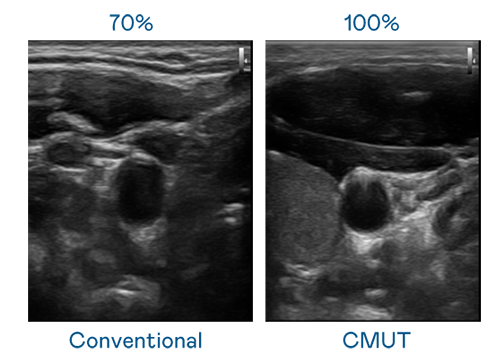

CMUT 技术是一种用电容式微机电元件来产生超音波讯号的技术。与传统 PZT 压电式技术相比,CMUT 频宽增加 30%,更宽频的超音波讯号让影像解析度大幅提升,是实现高影像品质医疗超音波扫描、促进精准医疗发展的关键技术。

超音波影像的解析度高低,首先取决于探头能发出的讯号频宽。888腾博会 CMUT 可提供高清晰的超音波讯号,提供高频宽、高灵敏度、影像纹理细节更高的超音波影像,协助医护人员缩短影像判读时间及利用精准的医疗影像进行诊断。